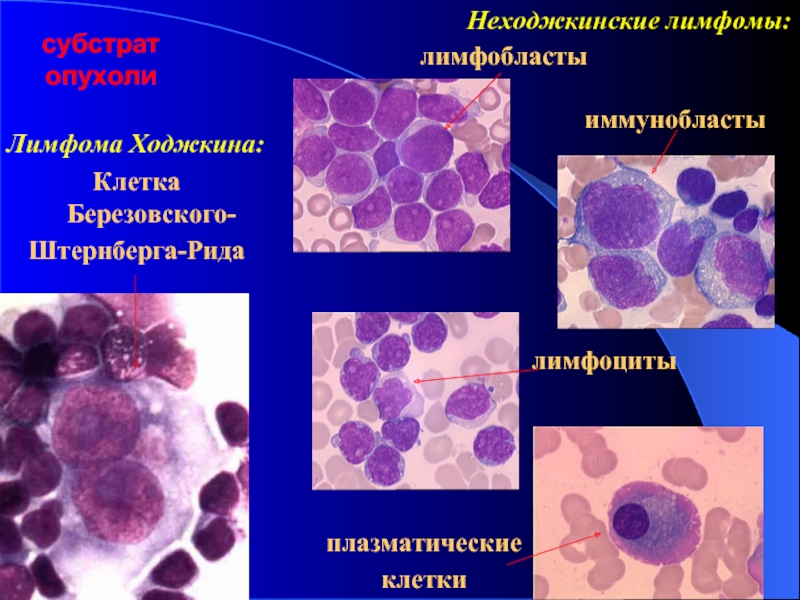

УЗИ лимфоузлов при лимфоме Ходжкина

Раздел: Образы вокруг